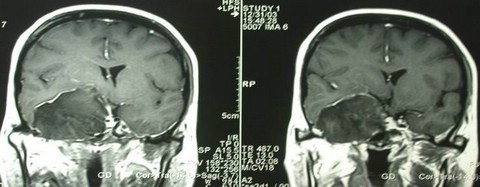

右CPA胆脂瘤

女性,49岁,右侧外展、动眼神经完全麻痹入院。右中颅窝巨大占位性病变。

术中证实为表皮样囊肿,予以包膜内全切。包膜大部剔除。图示术中情况。